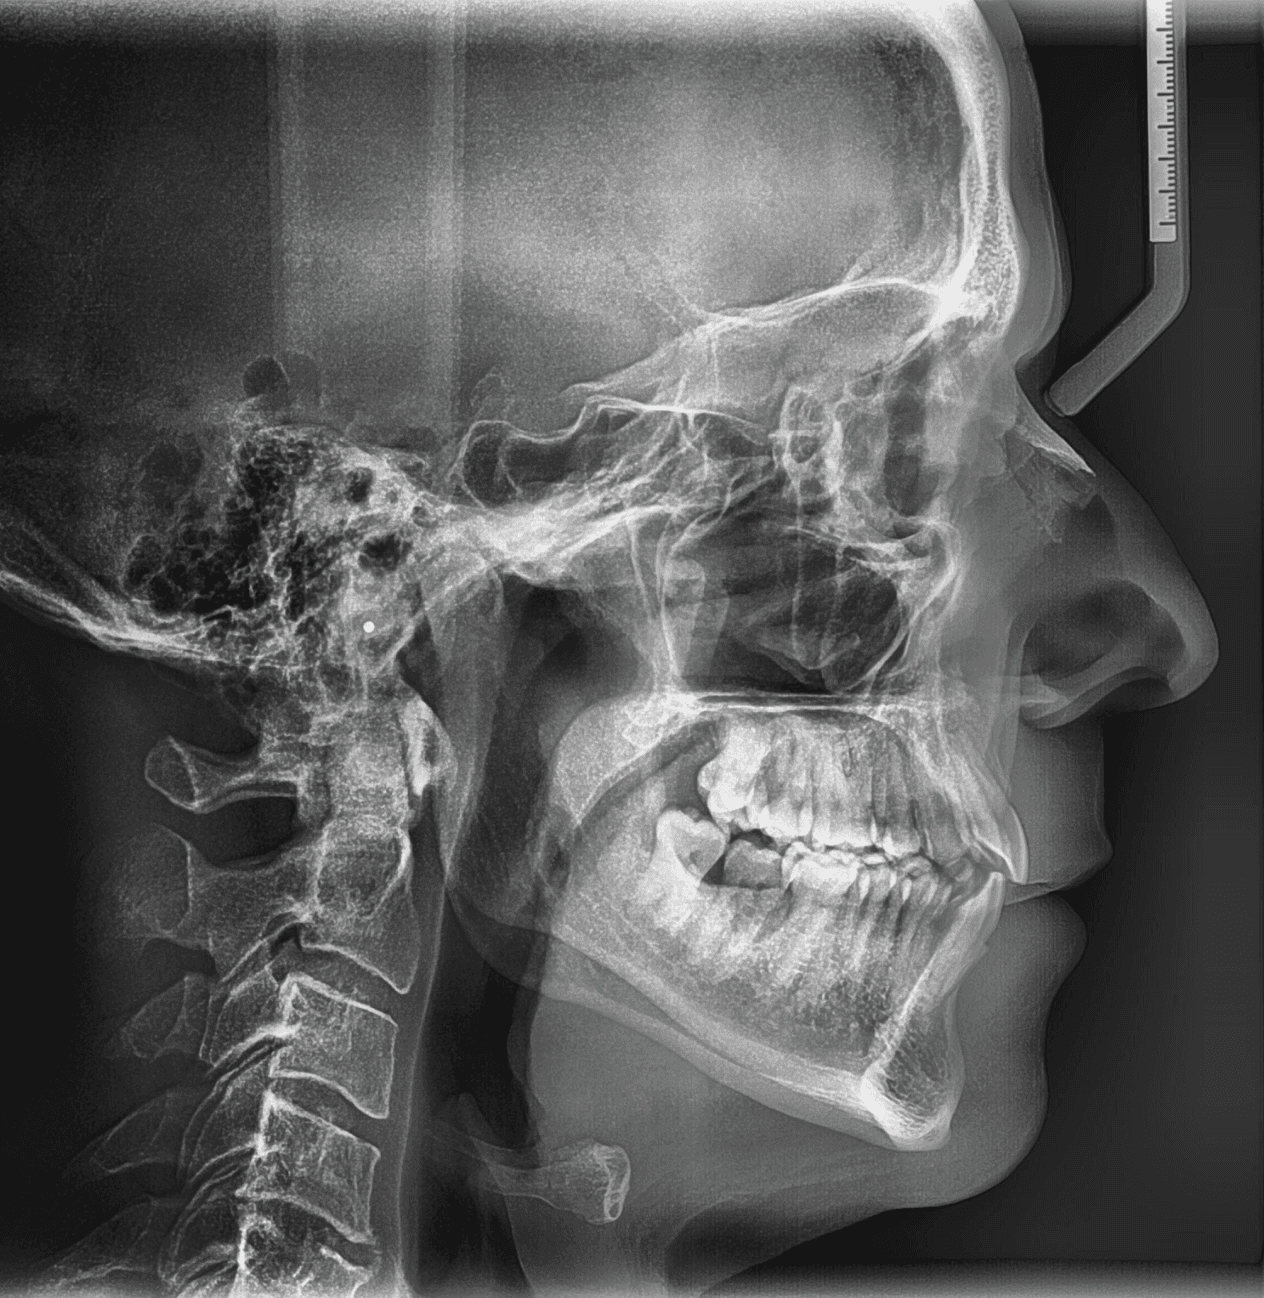

X-RAYS